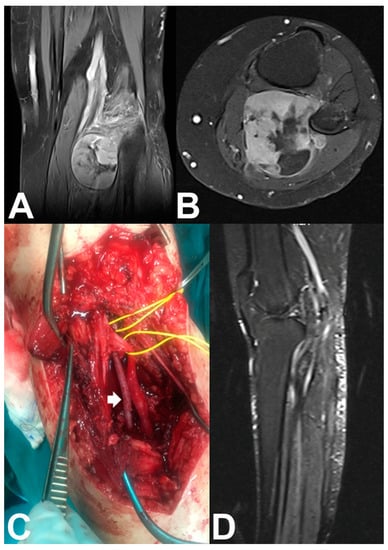

Figure 2. (A) Coronal and (B) axial T2-weighted MR images of the left knee of a 55-year-old woman with a popliteal fossa synovial sarcoma. (C) En bloc (marginal) tumor resection was done after identification and preservation of the peroneal and tibial nerves (lower vessel-loop), ligation without reconstruction of the popliteal vein, identification of the popliteal artery (upper vessel-loop), and arterial bypass reconstruction with the tibial artery using a contralateral great saphenous vein graft (white arrow) without venous bypass reconstruction. (D) Sagittal T2-weighted MR image shows tumor resection and limb preservation with patent anastomosis.